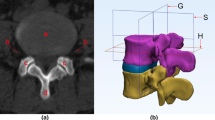

In the Mimics software 3D model, we identified the area where the centre ‘O,’ as projected by the angle ‘β,’ intersects with the facet joint on the same side. This intersection was designated as the focus point, represented by the letter ‘J.’ In the subsequent 3D model simulation of surgery, the area surrounding point ‘J’ served as the puncture fixation site for the Kirschner guide wire. Centred on the fixed Kirschner wire, a visible trephine was placed with a maximum diameter smaller than ‘d,’ ensuring it does not exceed the boundaries defined by ‘AB’ and ‘AC.’ Consequently, we identified the ‘J’ point as the safe central point during surgery, and the surrounding facet joint area as the safe zone (‘J’ point was showed in the supplementary material).

To precisely define the safe area around the ‘J’ point, we divided the facet joint into four equal quadrants using a 3D model in Mimics. The segmentation process included the following: (1) drawing a horizontal line at the upper vertex of the facet joint on the L5 vertebral body; (2) drawing a horizontal line at the lower edge of the facet joint under the L4 vertebral body; (3) drawing a vertical line from the lateral edge of the facet joint on the L5 vertebral body, perpendicular to the horizontal plane; (4) drawing a vertical line from the lateral edge of the exiting root, perpendicular to the horizontal plane. These steps produced four border lines by connecting the midpoints of lines 1 and 2, and lines 3 and 4. The resulting quadrants were labelled A, B, C, and D. The quadrant containing the ‘J’ point within the facet joint was specifically identified and recorded (Fig. 3).

Quadrant of the articular process joint where ‘J’ is located

In Endo-LIF, precise positioning can not only improve the efficiency of surgery, but also ensure the safety thereof. Li et al. [9] showed that the use of 18-gauge positioning mainly relies on fluoroscopy and surgeon experience; the requirements are high, and the selection of positioning points lacks anatomical data support. Although the “safe centre” point positioning method has corresponding anatomical data support, it is only described in the coronal plane [23]. The posterior bone mapped by the “safe centre” point was not included in the study by Li et al. [23]. During the operation, it was necessary to rely on the vertebral pedicle and sacrum as a reference for positioning points under fluoroscopy. This method was not easy to conduct. In a dataset of 40 cases, the authors demonstrated that, when the centre ‘O’ of the inscribed circle in Kambin’s triangle was abducted at the ‘β’ angle, it projected to the ‘J’ point. This point aligns with the initial Kirschner wire puncture location at the upper outer quadrant of the facet joint, showing high statistical significance (P < 0.001). The authors recommend inserting the initial Kirschner wire percutaneously into the upper outer quadrant of the facet joint under fluoroscopic guidance during surgery. After expanding the skin and soft tissue, the wire should be adjusted to an abduction angle of 32.02 ± 0.90° and aligned as parallel as possible to the intervertebral space before anchoring it within the facet joint bone. Using the Kirschner wire as a reference, the visible trephine is implanted and abducted at the same angle to guide bone resection and prevent disorientation during the procedure.

Finally, we suggest utilising the data from this study in transforaminal lumbar interbody fusion (TLIF). During the procedure, a guide Kirschner wire is percutaneously inserted into the upper outer quadrant of the facet joint at the safety centre point ‘J,’ guided by C-arm fluoroscopy. The wire is then adjusted to an abduction angle of 32.02 ± 0.90° and aligned parallel to the intervertebral space before anchoring in the bone. Subsequently, the skin and soft tissue around the Kirschner wire are dilated, and an 8-mm visible trephine is inserted at the same abduction angle. This technique enables the resection of the facet joint bone in a single step, efficiently creating the working channel while ensuring a safe distance from the exiting and traversing nerve roots (Fig. 7).

Mimics 3D simulation of the L4–L5 model. After the Kirschner wire is positioned in the upper outer quadrant of the facet joint, a visible trephine is centred on the wire to resect the facet joint and establish a working channel. The anteroposterior, anterior-posterior, left-lateral, and right-lateral views of a visible trephine abrasion of the articular synchondrosis to create a working channel are represented